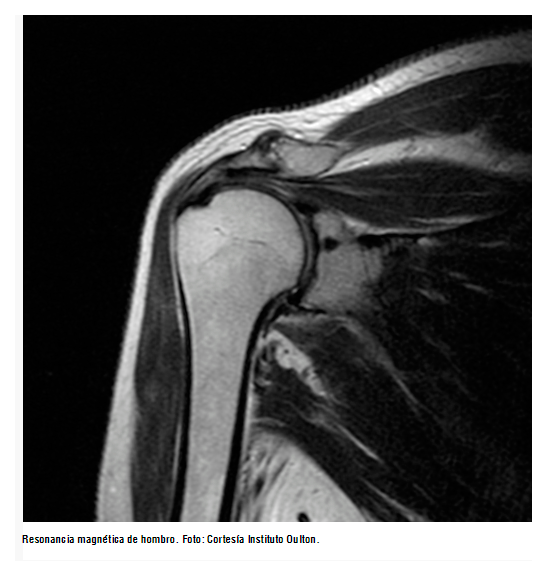

La resonancia magnética (RM) es indispensable en una gran parte de las afecciones médicas, no solo como método diagnóstico, sino también en el seguimiento de diversas patologías. En la actualidad, resulta muy útil para la solución diagnóstica de problemas traumatológicos, y las imágenes que se logran obtener, con un poco más de tiempo según las secuencias, son de alta calidad.

Por otro lado, ha aumentado su uso para visualizar las extremidades, y se ha establecido como una herramienta esencial para el diagnóstico preciso en los pacientes con trauma músculo esquelético. Sus principales ventajas incluyen excelente contraste tisular, alta resolución espacial y el no uso de radiación ionizante.

Aunque la radiografía permanece como la herramienta básica para el diagnóstico y planeación terapéutica en las fracturas óseas asistida por la tomografía pélvica, de columna, y trauma en las articulaciones grandes, hay circunstancias específicas que requieren de RM. Por ejemplo, los ligamentos, los tendones, las estructuras intraarticulares, como el cartílago y el menisco, y el daño intramedulares se ven en gran medida.